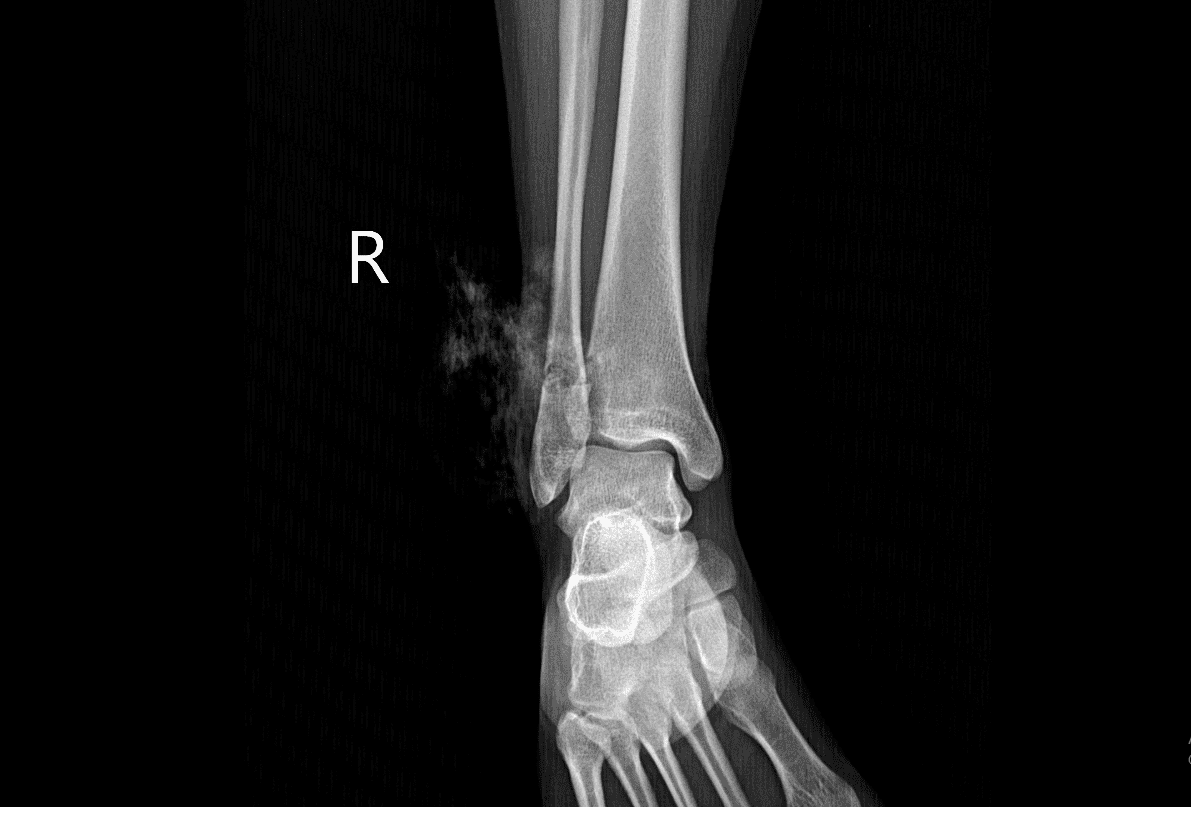

Sau thăm khám và thực hiện chụp X-Quang bệnh nhân được chẩn đoán: Gãy xương 1/3 dưới xương mác phải, gãy hở; vết thương hở tại cẳng chân và được chỉ định phẫu thuật kết hợp xương.

HÌnh ảnh chụp X-Quang của bệnh nhân